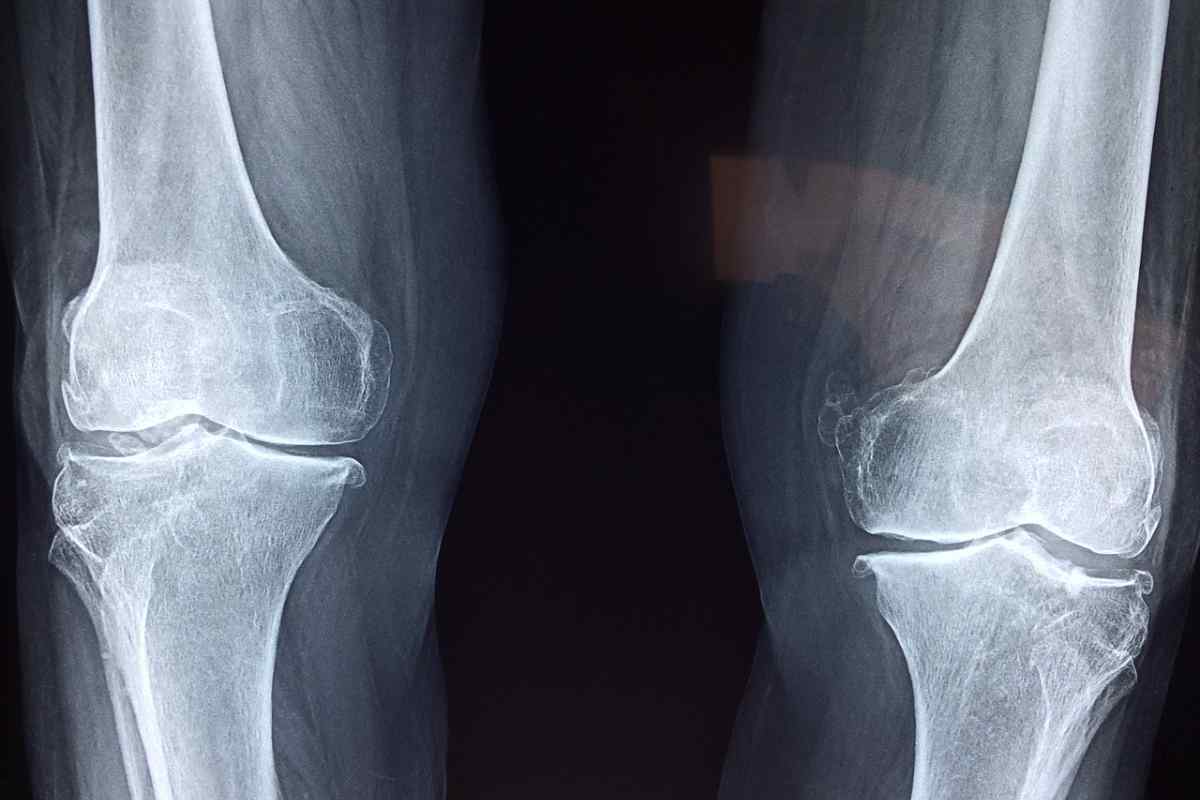

Parliamo di quello che ha colpito Andrea De Nicolao, cestista della Pallacanestro Cantù. Ieri si è sottoposto a un intervento in artroscopia a causa del mancato miglioramento delle condizioni del suo ginocchio.

“L’atleta Andrea De Nicolao è stato sottoposto nella giornata di mercoledì 19 febbraio a un intervento in artroscopia al ginocchio destro, perfettamente riuscito. L’équipe medica ha eseguito una pulizia articolare mirata a migliorare la tenuta dell’articolazione e a favorire una ripresa ottimale dell’attività sportiva.

I tempi di recupero stimati dopo l’operazione sono di circa 6 settimane, durante le quali il giocatore seguirà̀ un protocollo riabilitativo specifico. Lo staff medico del Club monitorerà̀ attentamente ogni fase del recupero, valutando le reazioni e gli eventuali sintomi nelle fasi di riabilitazione che ne determineranno l’effettiva durata, al fine di garantire un rientro in campo nelle migliori condizioni e nel minor presto possibile”.